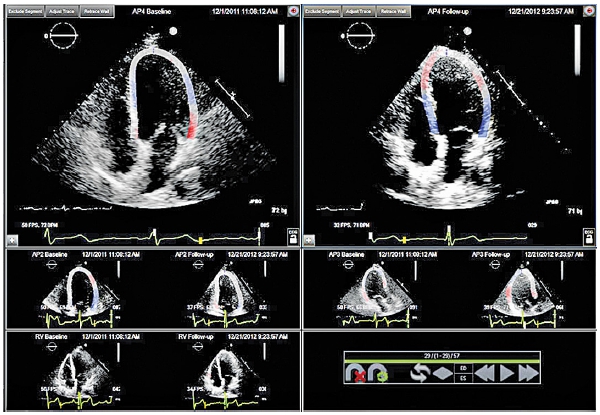

Noi am lucrat printr-o teză de doctorat (Dr. Anca Maria Popară-Voica) la „determinarea efectelor toxice ale chimioterapiei asupra cordului”.

Concluziile studiului nostru se referă la necesitatea monitorizării active a pacienţilor ecografici care primesc tratament antiangiogenic şi a colaborării strânse oncolog-cardiolog.

Tratamentul antiangiogenic induce la jumătate din pacienţi agravarea HTA preexistentă şi apariţia HTA de novo plus reducerea parametrilor de funcţie sistolică a ambilor ventriculi.

Totuşi disfuncţia cardiacă trebuie privită ca o consecinţă a toxicităţii miocardice intrinseci a terapiei in discuţie, HTA preexistentă fiind factorul permisiv/precipitant major al cardiotoxicității acestei terapii.

Desigur – studiul tutror acestor factori imagistici în cardio-oncologie este în plină desfășurare și rezultatele sale sunt așteptate.